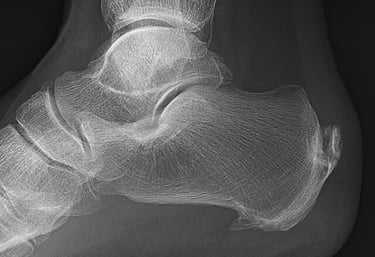

A veces se encuentra mediante radiografía un espolón calcáneo, que es un pico que se forma en la inserción de la fascia plantar. A primera vista parece un elemento dañino y que se puede clavar en la planta del pie, ya que esto coincidiría con el dolor tipo punzante de la fascitis. Aunque no necesariamente es algo malo.

Cuando existe un proceso inflamatorio o degenerativo como es el caso de la fascitis plantar, pueden generarse depósitos de calcio en la inserción de la fascia como un intento de adaptación de la zona. De hecho, por su forma y disposición, es espolón no se clava en ningún sitio, sino que sufre fuerzas de tensión.

No sólo eso, sino que se ha demostrado que a mayor tamaño del espolón, menores niveles de dolor tiene la persona.